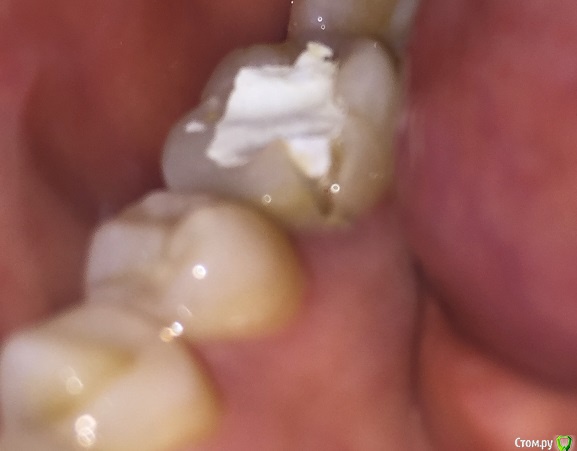

Craysley@rambler.ru Опубликовано 16 июля, 2016 Поделиться Опубликовано 16 июля, 2016 (изменено) Здравствуйте! Сегодня ходила на лечение зубного канала шестерки. Этот зуб до этого мне лечили лет 5 назад. Врач просверлил пломбу, кое-как добрался до корня зуба, вколол какие-то лекарства туда и установил временную пломбу. Сказал, что лекарство как должно постоять там хотя бы неделю. Однако, этим же днем, когда я жевала мягкую булочку, откололся кусочек стенки этого зуба.Вины стоматолога тут в любом случае нет, до этого там по линии разлома были две трещинки. Вроде с другой стороны тоже имеется трещина. Что теперь будет с зубом? Можно ли будет его восстановить пломбой? Прилагаю рентген зуба до сегодняшнего лечения. Изменено 16 июля, 2016 пользователем Craysley@rambler.ru Ссылка на комментарий

red_butler Опубликовано 16 июля, 2016 Поделиться Опубликовано 16 июля, 2016 Похоже просто скололся фрагмент старой пломбы, обратитесь в ближайшее время к своему врачу, временная реставрация должна быть герметичной. Ссылка на комментарий

St. Опубликовано 16 июля, 2016 Поделиться Опубликовано 16 июля, 2016 Что теперь будет с зубом? Можно ли будет его восстановить пломбой? Пломбой - нет. Нужна будет коронка. Про добавить временно пломбу пока с лекарством ходите - поддерживаю. Ссылка на комментарий

St. Опубликовано 16 июля, 2016 Поделиться Опубликовано 16 июля, 2016 До скола зубу тоже показана была коронка, т.к. он без нерва и с очень большой пломбой. С новой пломбой вы рискуете сломать стенку зуба на не прогнозируемую глубину. И тогда как повезет - или коронка или удаление зуба. 1 Ссылка на комментарий

red_butler Опубликовано 16 июля, 2016 Поделиться Опубликовано 16 июля, 2016 Выбор не велик, или коронка на зубе, либо на импланте. Ссылка на комментарий